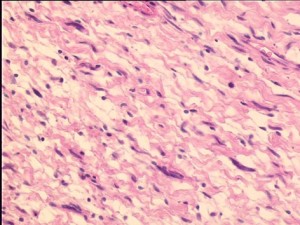

Who grade i

Who grade i 115 фотографий